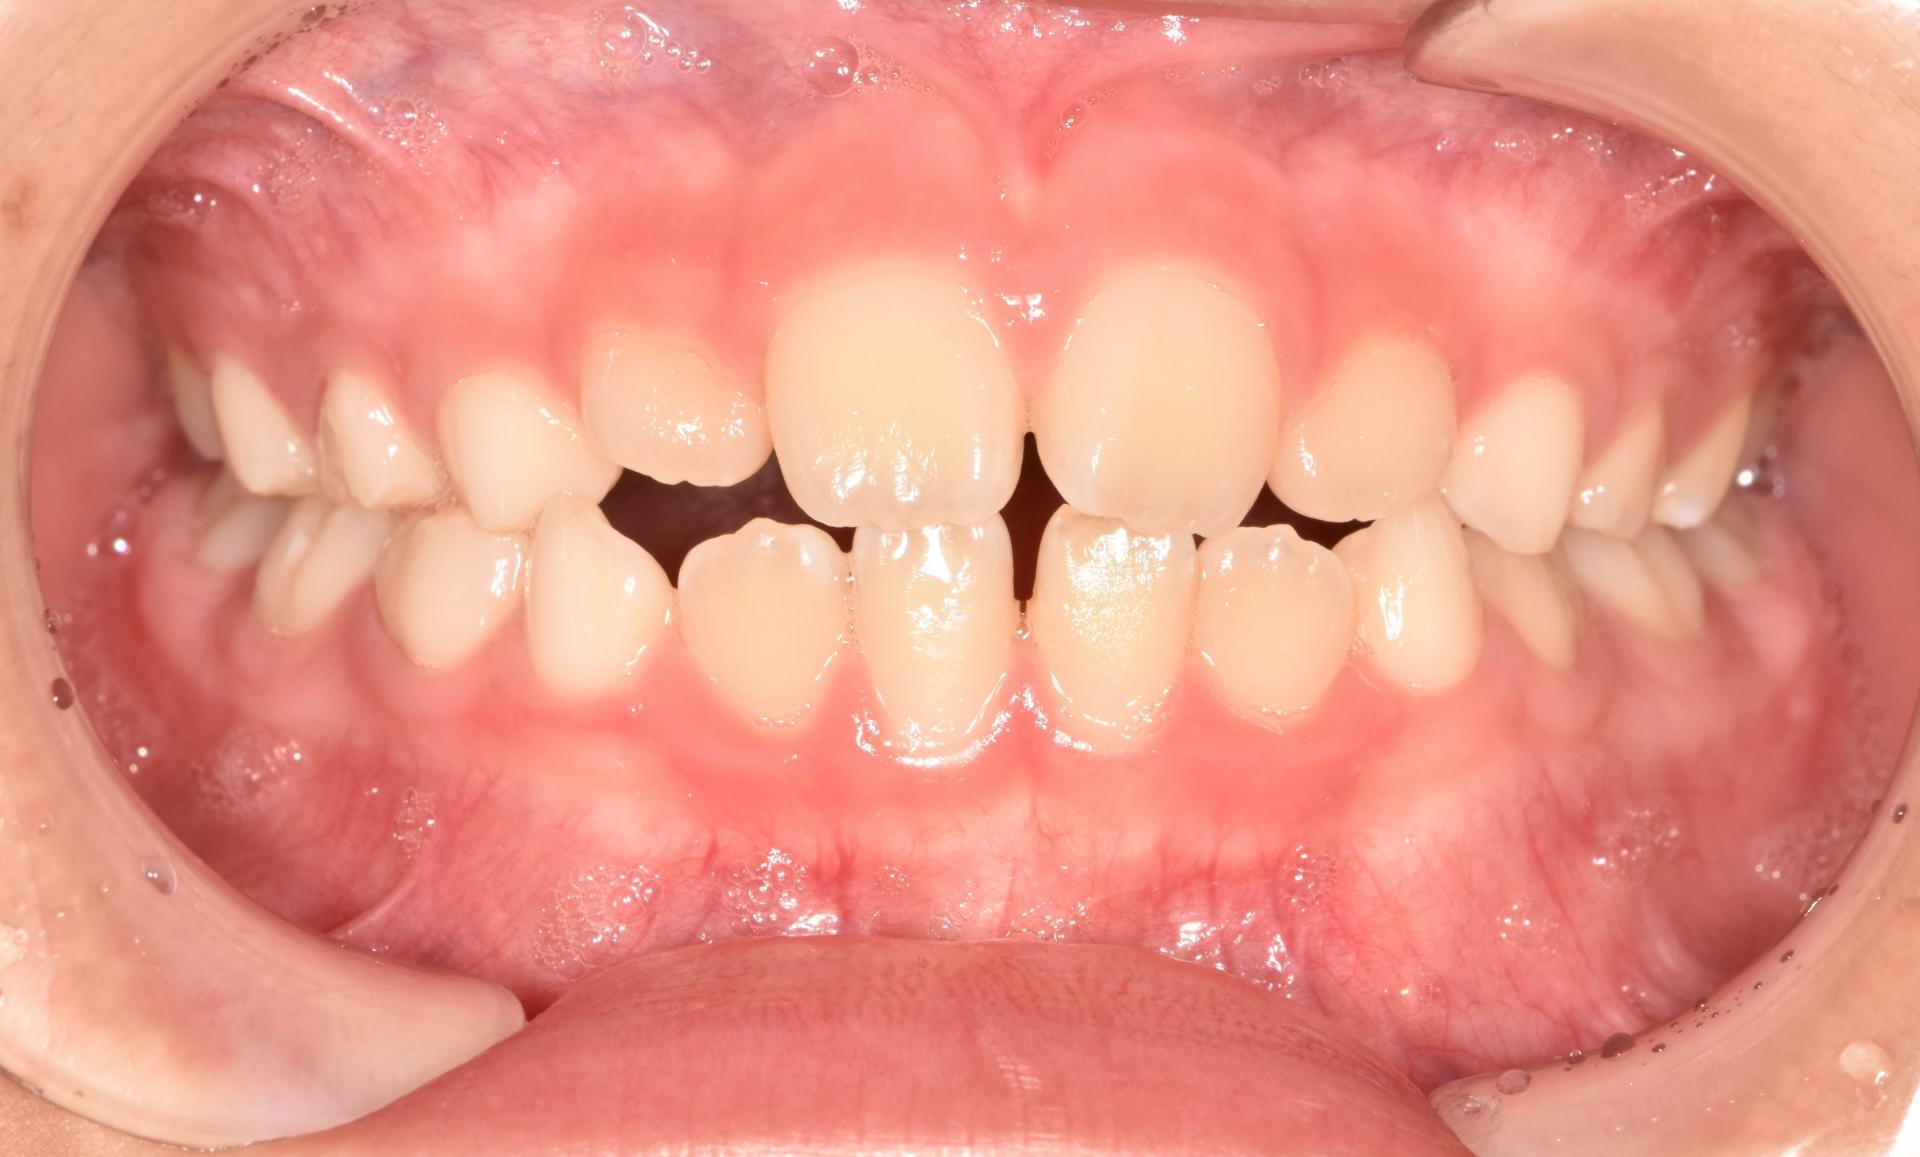

초진 사진입니다. 고르지 못한 앞니와 치아의 회전으로 인한 위아래 앞니의 부딪힘이 발생하고 있습니다. 또한 위아래 앞니의 뻐드러짐과 돌출이 보입니다.